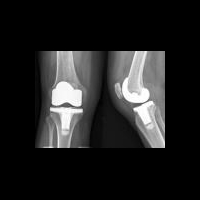

Ортопедические имплантаты с наноалмазным покрытием

Наноалмазное покрытие ортопедических имплантатов предупреждает воспаление вокруг металлических и полимерных материалов протезов. Результаты исследования имплантатов с наноалмазным покрытием опубликованы в журнале Acta Biomaterialia.

В современной травматологии прослеживается тенденция к применению имплантатов с максимальной износоустойчивостью и безопасностью. Ученые из Университета штата Алабама в Бирмингеме исследуют влияние наноалмазного покрытия на степень износоустойчивости протезов. Продуты износа протезов вызывают боль и ограничение подвижности. Это обусловлено действием макрофагов, клеток "чистильщиков" в человеческом организме, которые поглощают частицы металлических поверхностей имплантата и затем выделяют биологически активные вещества, вызывающие воспаление и его классические признаки: отек и боль. Хроническое воспаление приводит к разрушению окружающей кости и неустойчивости соединения, то есть требуется повторная операция. Наноалмазное покрытие остановливет износ металлических покрытий и образование металлических частиц, однако образуются мелкие наноалмазные частицы.

Американские ученые после исследований in vitro взаимодействия наноалмазных частичек с макрофагами, пришли к заключению: продукты износа обычного размера и в обычной концентрации не могут привести к воспалению и токсическим эффектам. В сравнении с традиционными металлическими и полимерными имплантатами, макрофаги, поглощающие частицы наноалмазов, секретируют меньше биологически активных соединений. В исследовании было изучено воздействие синтетических наноалмазов различных размеров (6, 60, 100, 250 и 500 нм), в различных концентрациях (0, 10, 50, 100, 200 микрограмм на миллилитр). Было обнаружено, что при концентрации менее 50 мкг/мл (именно такова их обычная концентрация в качестве продуктов износа искуственных суставных поверхностей), наноалмазы не оказывают токсического воздействия на макрофаги. При концентрации свыше 200 мкг/мл жизнеспособность макрофагов падала до 50 процентов, независимо от размера частиц. Также было обнаружено, при воздействии наноалмазных частиц снижалась экспрессия генов, ответственных за развитие воспаления: за образование ФНО-α фактора некроза опухоли-альфа, интерлейкин-1β, хемокин Ccl2 и фактора роста тромбоцитов.

«Наши результаты свидетельствуют в пользу того, что наноалмазы действительно нетоксичны для живых клеток», – комментирует доктор Виной Томас (Vinoy Thomas), научный сотрудник кафедры физики Колледжа искусств и наук (College of Arts & Sciences) UAB. «Предыдущие работы по суставным поверхностям с наноалмазным покрытием показали заметное снижение объема продуктов износа по сравнению с протезами первого поколения из сплава и полиэтилена, но работа по обеспечению гарантии их безопасности продолжается», – подводит итоги старший автор исследования Йогеш Вохра (Yogesh Vohra), Ph.D., директор Центра наноматериалов и биоинтеграции (Center for Nanoscale Materials and Biointegration) UAB. «Мы надеемся, что уменьшение объема износа и размера частиц, ожидаемое для алмазных суставов, станет их большим преимуществом перед обычными ортопедическими протезами».